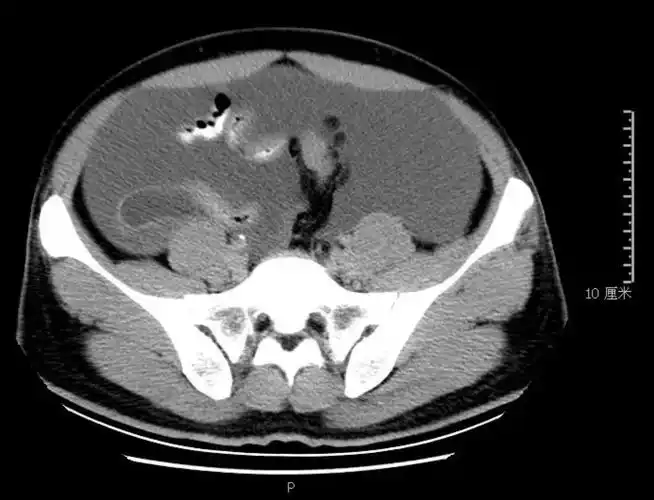

图一:左侧输尿管上段扩张伴左肾轻度积水.